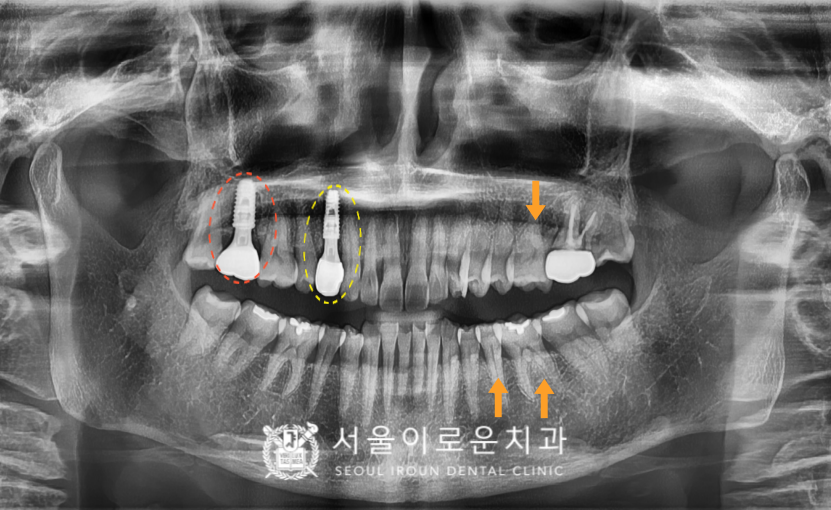

확인해 보았더니

노란색 동그라미 표시의

오른쪽 위 첫 번째 작은 어금니(#14)에서

불편감을 보이셨는데요.

x-ray 상으로는 크랙 라인이

또렷하게 관찰되지는 않지만

구내에서 확인하였을 때

상당히 깊게 크랙이

진행된 것으로 보였으며

타진 반응에도 통.증이 있었습니다.

안타깝게도 치아가 둘로 쪼개져

예후가 좋지 않아

발치를 해야 하는 상황이었답니다. (ㅠㅠ)

그리고 해당 치아 뿐만 아니라

다른 부위에서도

문제가 있는 부위들을

발견할 수 있었는데요…!

주황색 동그라미 표시의

오른쪽 위 두 번째 큰 어금니(#17)의

기존 보철하였던 치아가

동요도가 심하고, 뿌리까지 염증이

진행된 것을 확인할 수 있었습니다.

그리고 주황색 화살 표시의

왼쪽 위 첫 번째 큰 어금니(#26),

왼쪽 아래 두 번째 작은 어금니(#35)와

첫 번째 큰 어금니(#36)엔

치아와 잇몸 사이인

치경부 부위가 움푹 파여있는

치경부 마모증을 관찰할 수 있었는데요.